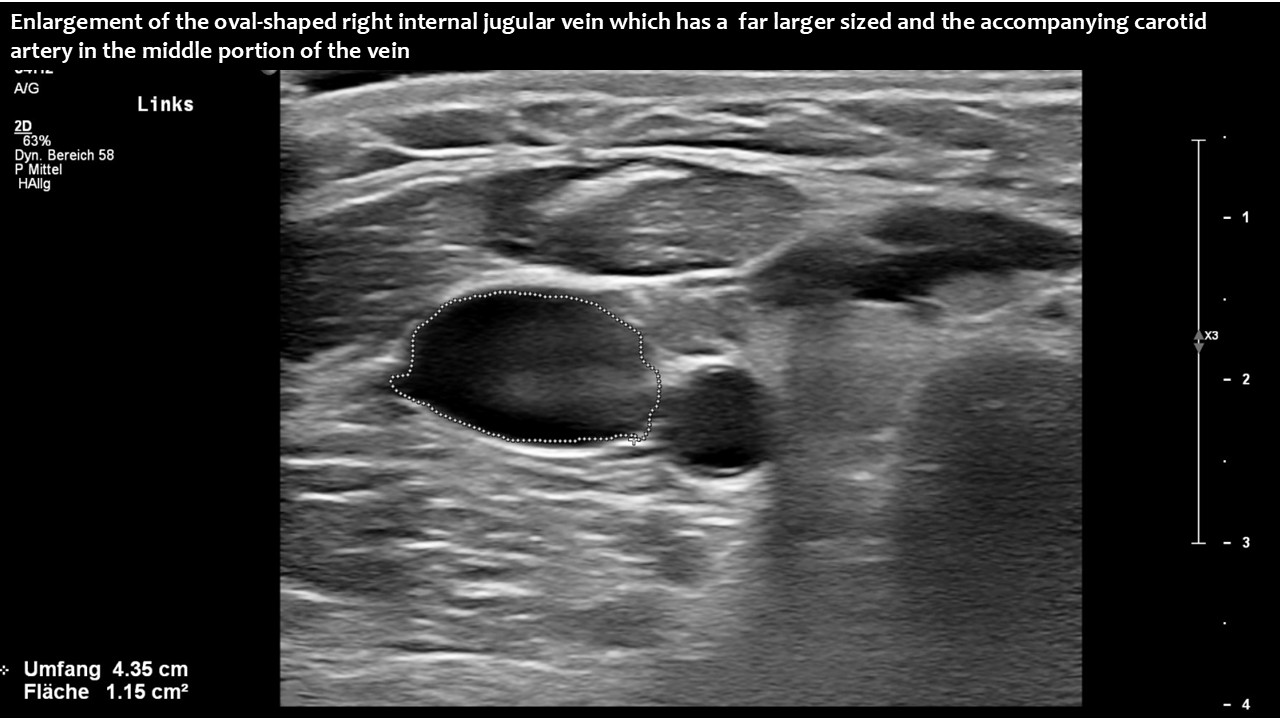

However, in this patient, both jugular veins were compressed. The middle portion of the internal jugular vein was pushed ventrally by the increased cervical lordosis on both sides, becoming squeezed between the carotid artery and the sternocleidomastoid muscle.

Consequently, blood had difficulty leaving the skull, resulting in continuously increased pressure and severe headaches, as well as other neurological dysfunction. The left side was more affected due to the double compression. This was clearly demonstrated by four-dimensional volume flow measurements in both jugular veins.